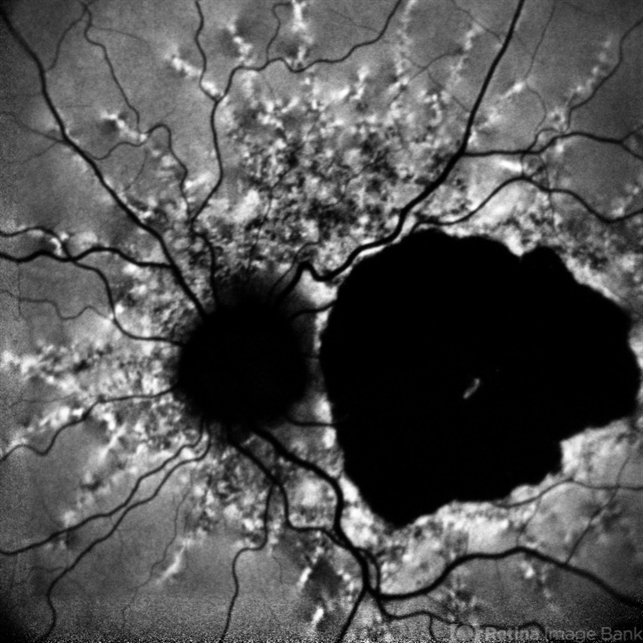

- Fundus autofluorescence photograph of a 65-year-old male with numerous narrow, irregular streaks radiating in a circumferential pattern within the posterior pole with macular atrophy.